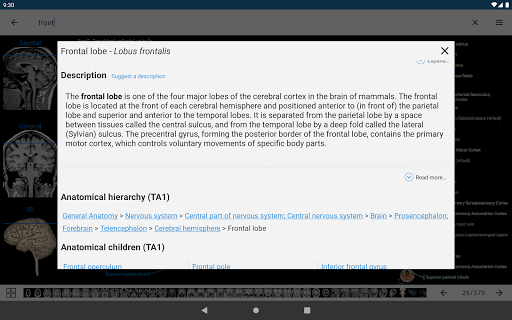

* تحسين رؤية تعريفات الأجزاء التشريحية

* تصفح بين الأجزاء التشريحية باستخدام روابط الوصف

- يتم الآن عرض المصطلحات المتعلقة بالهيكل التشريحي في عرض التفاصيل - تمت إضافة